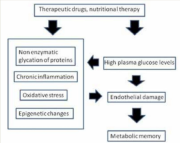

| 06:37, 24 בספטמבר 2023 | התפשטות1.png (קובץ) |  |

184 קילו־בייטים | Motyk | 1 | |